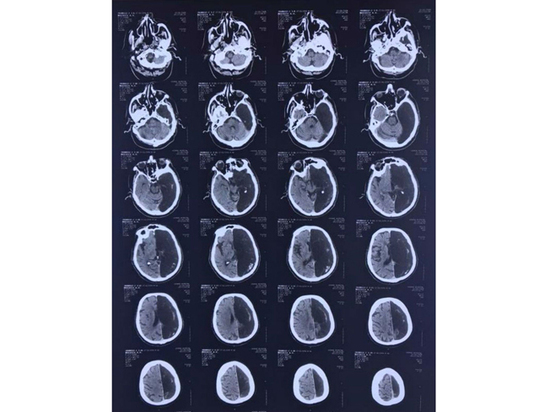

Когда радиологи сделали ему КТ, то некоторое время пребывали в недоумении - у пенсионера отсутствовала та часть мозга, где произошла та самая ишемическая атака. Вместо левого полушария на снимке зияла черная "дыра".

Неврологи сделали вывод, что функции всего мозга у этого человека всю жизнь выполняло только оставшееся правое полушарие. Ишемическая атака вскоре сошла на нет, функции конечностей восстановились, и мужчину отпустили домой.